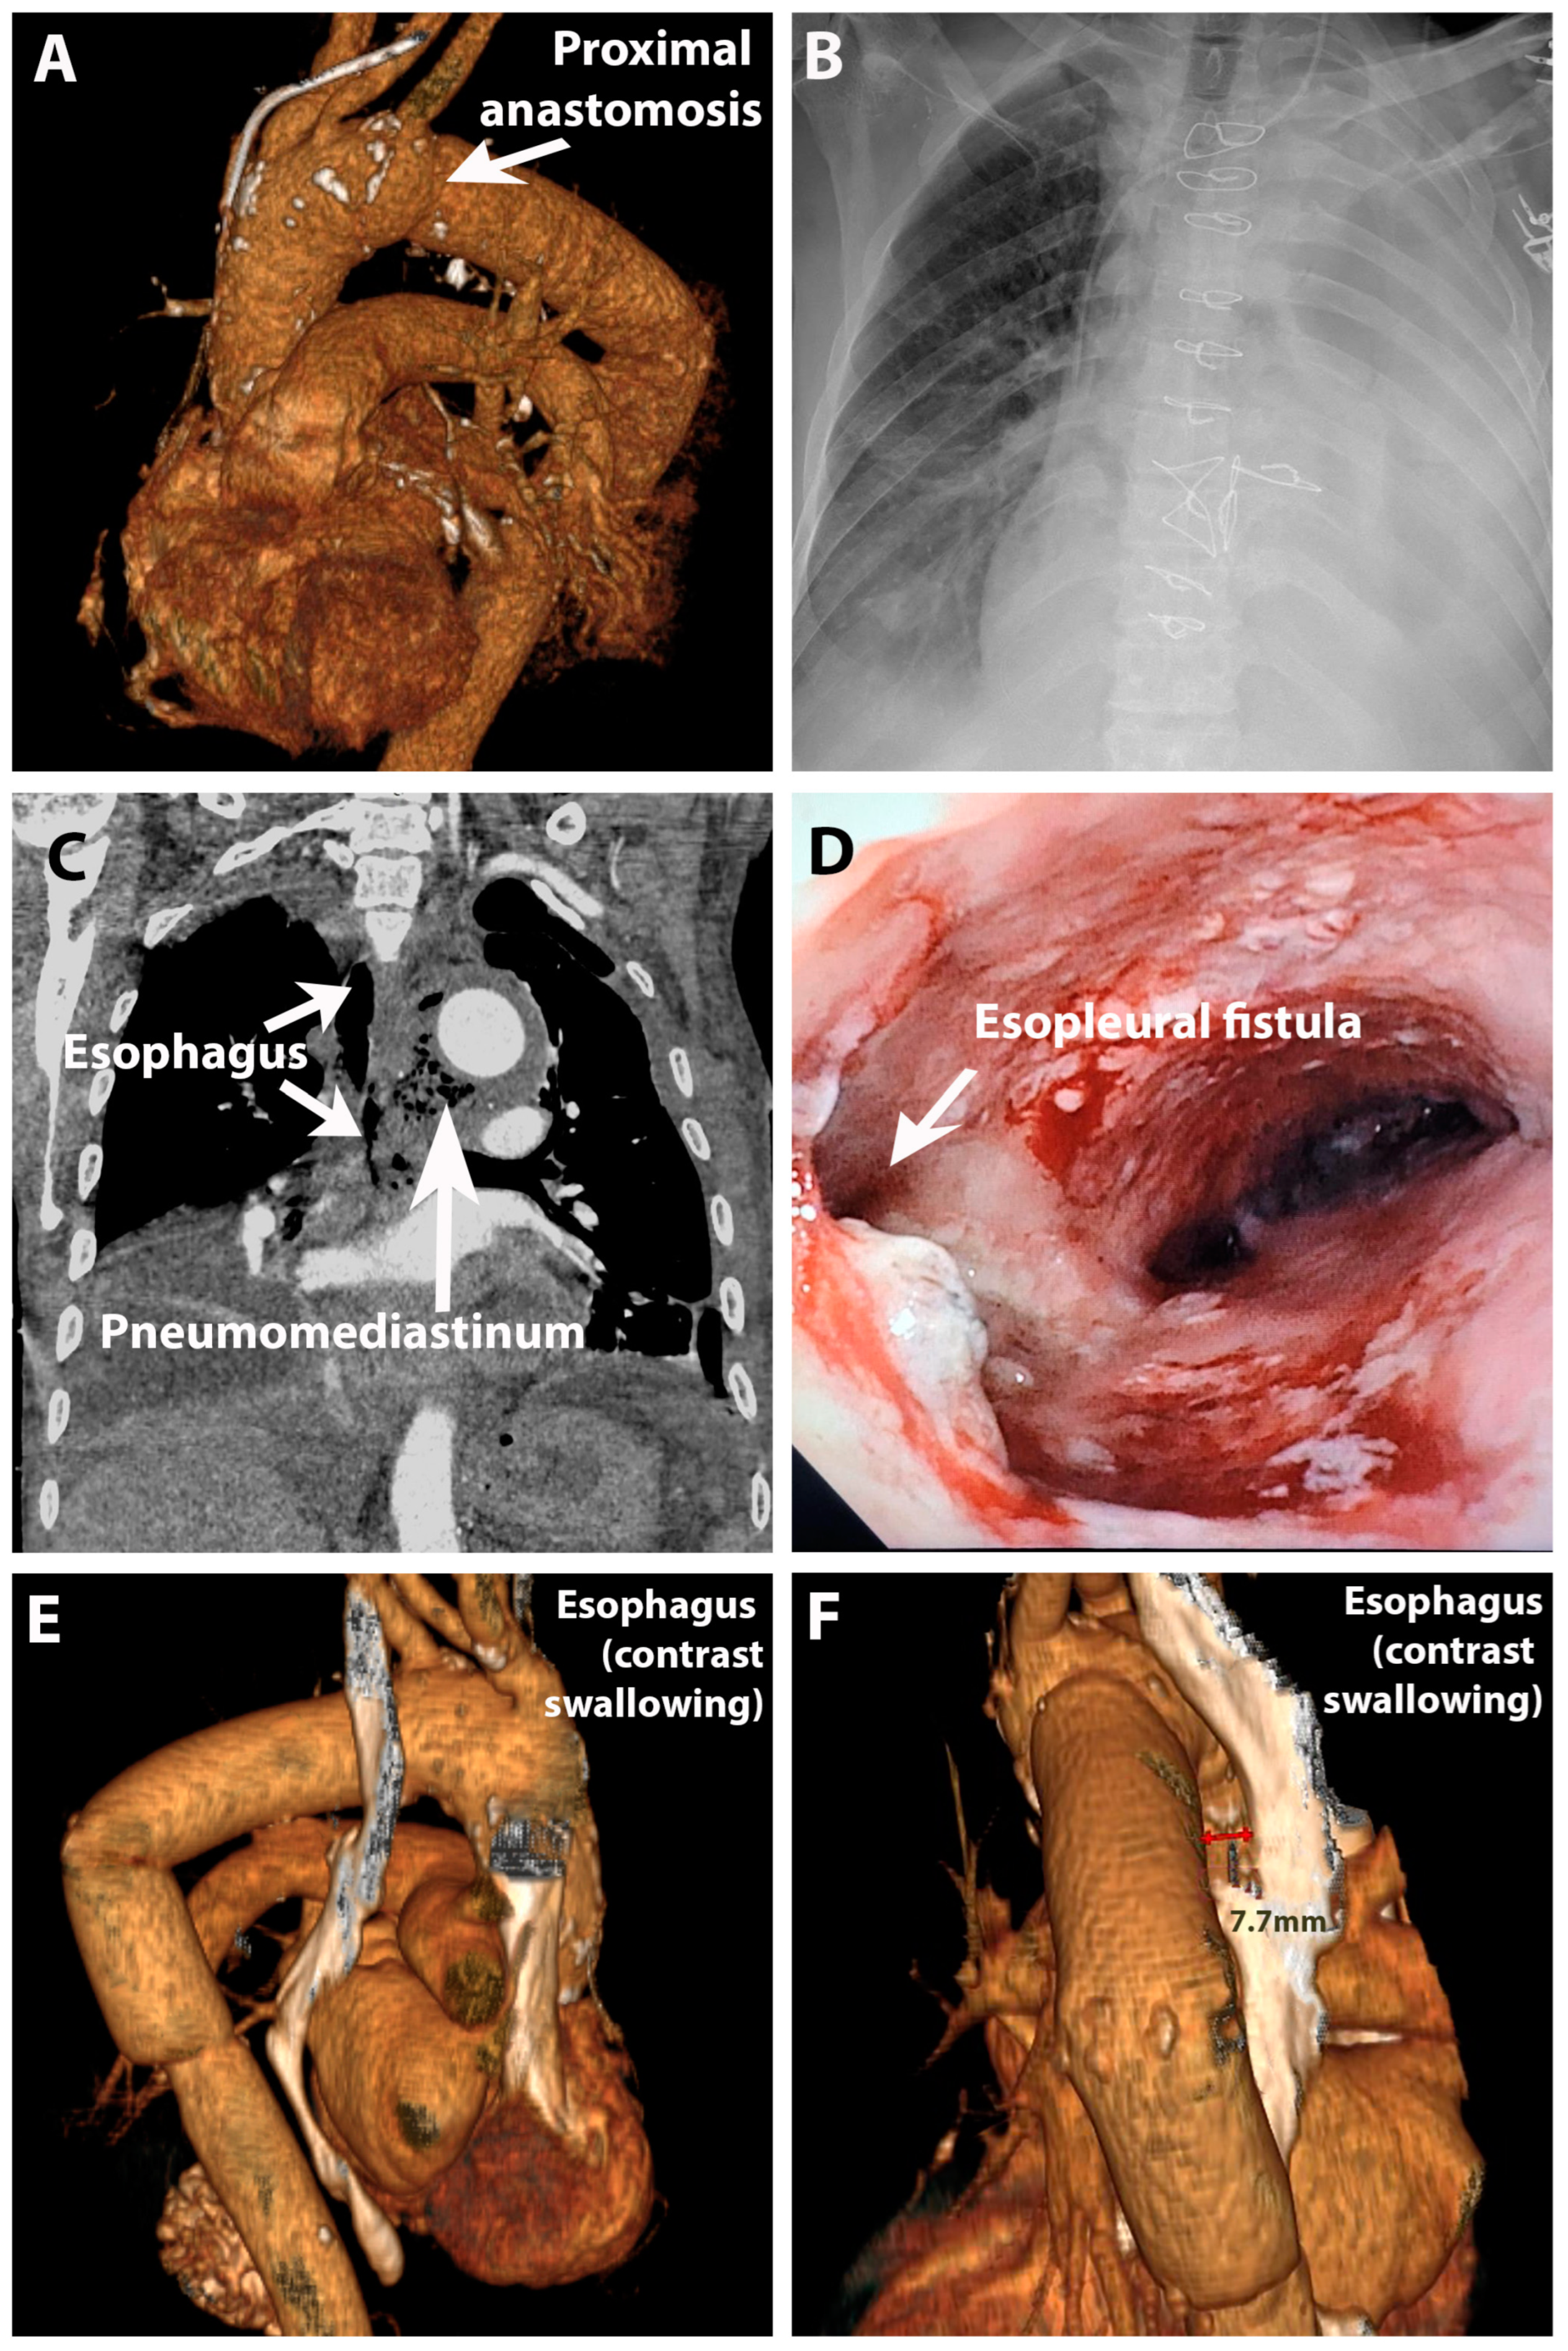

2. Case Presentation